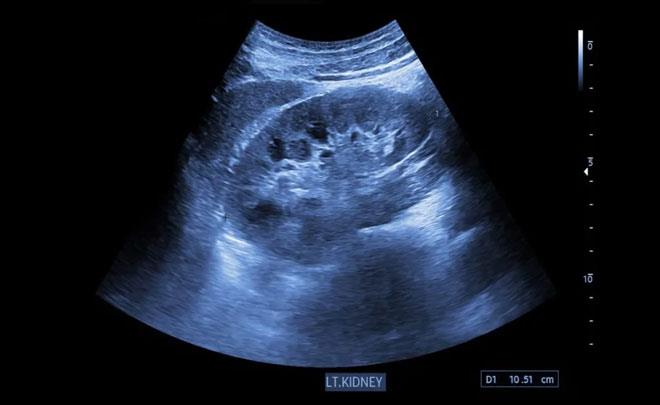

بەردی گورچیلە دەتوانرێت بە سۆنەر دەستنیشان بکرێت چونکە بەردەکان تایبەتمەندی تایبەتیان هەیە کە وا دەکات بە ئاسانی لە کاتی وێنەگرتندا دەستنیشان بکرێت، بەردی گورچیلە وەک پەڵەیەکی سپی گەش دەردەکەوێت لە سۆنەردا.

- سۆنەر دەتوانێت بەرد لە ئەم شوێنانە دەستنیشانبکات:

1- حەوزی گورچیلە.

2- ژوورەکانی گورچیلە.

3- هەندێک جار بەشی سەرەوەی میزڵدان (بەڵام بینینی بەردی میزڵدان سەختترە).

- سۆنەر دەتوانێت چەند نیشانەیەکی بوونی بەردی گورچیلە دەستنیشان بکات، وەک:

1- ئاوسانی گورچیلە.

2- زیادبوونی قەبارەی گورچیلە.

3- دیاریکردنی بەردەکان ≥ 4-5 ملم.